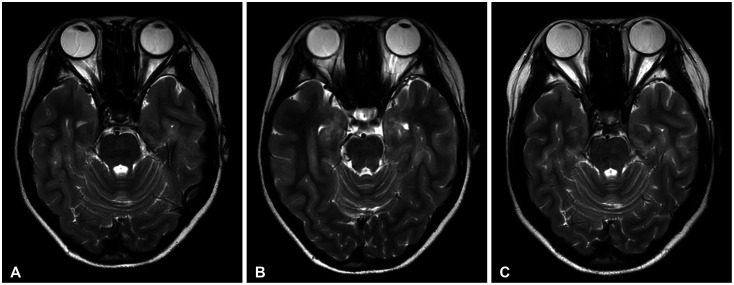

Differential diagnosis of focal brainstem lesions detected on MRI is challenging, especially in young children. Formerly, brainstem gliomas were classified mainly based on MRI features and location. However, since 2016, the World Health Organization's brainstem lesion classification requires tissue biopsy to reveal molecular characteristics. Although modern techniques of stereotactic or navigation-guided biopsy ensure accurate biopsy of the lesion with safety, biopsy of brainstem lesions is still generally not performed. Here, we report a focal brainstem lesion mimicking brainstem glioma in a 9-year-old girl. Initial MRI, MR spectroscopy, and 11C-methionine positron emission tomography (PET) features suggested low-grade glioma or diffuse intrinsic pontine glioma. However, repeated MR spectroscopy, perfusion MRI, and 18fluorodeoxyglucose PET findings suggested that it was more likely a non-tumorous lesion. As the patient presented not with a neurological manifestation but with precocious puberty, the attending oncologist chose to observe with regular follow-up MRI. The pontine lesion with high signal intensity on T2-weighted MRI regressed from the 6-month follow-up and became invisible on the 1.5-year follow-up MRI. We reviewed brainstem glioma-mimicking lesions in the literature and discussed the key points of differential diagnosis.